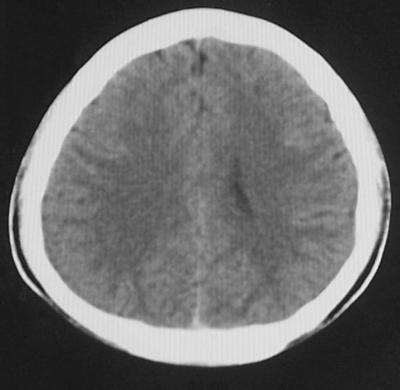

增强后

患者、男、18y,头痛5天入院。

左小脑、右丘脑区低密度影,无明显强化及占位表现,男18y,先考虑脑部炎性病变,如脑炎、血行播散性感染等,建议结合临床如脑脊液检验。

单独看左侧小脑半球的不规则形囊性低密度灶,从发病部位、年龄以及无强化、无占位效应的特点可以考虑毛细胞瘤型星形细胞瘤。同样,如果单独看右侧丘脑的近圆形低密度,也可以考虑囊变形星形细胞瘤。只是胶质细胞瘤一般为单发直接浸润、蔓延生长,而不是在脑内同时出现多个病灶,且瘤周没有一点儿水肿,暂时不予以考虑。

同时,现在已经进入冬天,一氧化碳中毒也需要考虑进去。不知道增强是什么时间做的,与平扫间隔几天?如果中间时间比较久而且进行吸氧等治疗,则平扫所示右侧颞叶密度比较低、右侧小脑半球以及脑桥也似有片囊状低密度,但在增强却没有发现就可以比较合理的解释了。